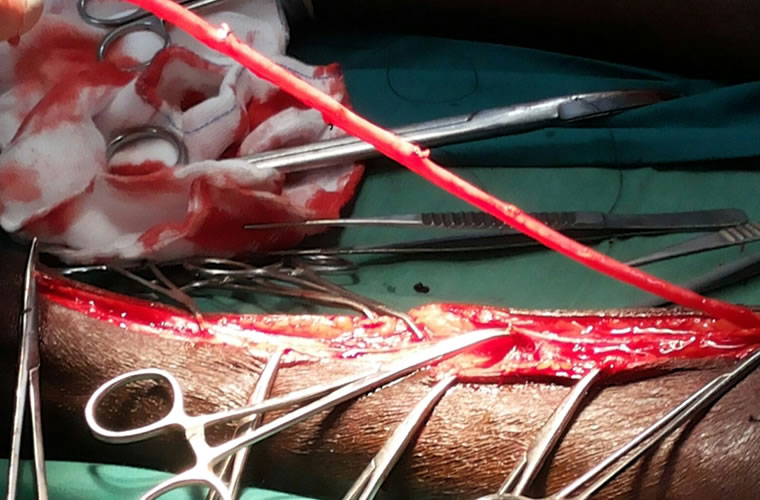

Dr.DineshShanmugaSundaram is specialized himself in each & every part of Cardiovascular & Thoracic Surgery both in Adult & Paediatric or Congenital Heart Diseases. He is both an ethical & academic surgeon,changed the trend in Cardiac Surgery to fast & safe level, as prolonged procedures in Cardiac Surgery increases postoperative complications. We aim at decreasing perioperative complications to the maximal level. Read More